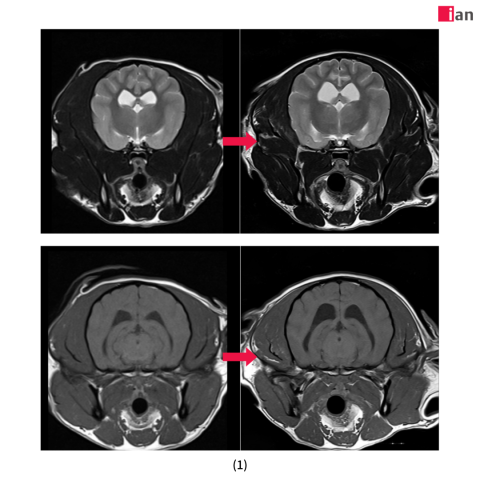

AI 도입 후 품질이 개선된 MRI 영상 사진

2023년 말 최첨단 AI MRI 소프트웨어를 도입한 이안동물의학센터는 촬영 시간 단축과 영상 품질 극대화라는 두 마리 토끼를 동시에 잡았다. 딥러닝 알고리즘을 통한 이미지 재구성과 노이즈 제거, 선명도 향상은 보다 신속하고 정확한 진단을 가능하게 했으며, 보호자와 반려동물 모두에게 높은 만족도를 제공하고 있다.

특히 AI 소프트웨어 도입 이후 촬영 시간이 기존 대비 최대 절반으로 줄어드는 등 검사 효율성이 크게 향상됐다. 이는 보호자들의 시간적 부담을 덜어줄 뿐 아니라 환자의 마취 시간 단축으로 검사 안전성을 더욱 높이는 효과를 가져왔다. 또한 이미지 퀄리티 향상으로 정밀한 판독이 가능해져 질병의 조기 발견과 정확한 진단을 통한 치료 전략 수립에 커다란 진전을 이뤄냈다. 여기에 이안동물의학센터 전담 마취팀의 철저한 관리까지 더해져 반려동물 검사 전 과정에서 신뢰도 높은 의료 서비스를 제공하고 있다.